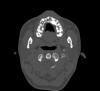

persona Опубликовано 12 октября, 2008 Автор Поделиться Опубликовано 12 октября, 2008 (изменено) Кроме того, проходил КТ. Выкладываю несколько срезов в области клыка. Изменено 12 октября, 2008 пользователем persona Ссылка на комментарий

Force Опубликовано 12 октября, 2008 Поделиться Опубликовано 12 октября, 2008 Кроме того, проходил КТ. Выкладываю несколько срезов в области клыка. А кто из врачей делал Вам трг перед планированием с расчетом? а расчет моделей делали? Ссылка на комментарий

Премоляр Опубликовано 14 октября, 2008 Поделиться Опубликовано 14 октября, 2008 Хм, честно говоря, у меня тоже небольшие сомнения вызывала возможность отцентровки при таком лечении.Т.е. вы за вариант лечения с имплантом? Но в этом случае точно придется удалять ретинированный клык, а при 2-ом плане лечения его можно было бы не трогать.Поставить в зубную дугу ретенир.клык будет очень очень травматично и сложно.И оставлять "просто так" клык тоже нельзя-т.к. со временем вокруг клыка может образоваться киста.(а может и нет...). Возможно целесообразнее удалить нижнюю 4ку справа(коррекция центра) и выравнивание зубов на вер.чел+последующая реставрация 4 ки сверху справа. И еще-сделать КТ для определения точной локализации ретенир.зуба(решения вопроса о его дальнейшей судьбе) Ссылка на комментарий

persona Опубликовано 14 октября, 2008 Автор Поделиться Опубликовано 14 октября, 2008 Поставить в зубную дугу ретенир.клык будет очень очень травматично и сложно.И оставлять "просто так" клык тоже нельзя-т.к. со временем вокруг клыка может образоваться киста.(а может и нет...). Возможно целесообразнее удалить нижнюю 4ку справа(коррекция центра) и выравнивание зубов на вер.чел+последующая реставрация 4 ки сверху справа. И еще-сделать КТ для определения точной локализации ретенир.зуба(решения вопроса о его дальнейшей судьбе)Спасибо большое за ответ. Только я не совсем понял насчет 4-ок. Может имелись в виду не правые, а левые 4-ки? Если так, то это получится в точности 2-ой вариант из тех, что я написал в первом посте. Ретинированный клык все врачи кроме одного рекомендуют не трогать, т.к. пока не беспокоит и корней других зубов вроде не задевает. КТ я сделал. Несколько срезов выложены во 2-ом посте. Если надо, могу выложить еще, но они все горизонтальные. Также есть еще снимок с 3-мерным изображением, но не думаю, что там лучше видно. Ссылка на комментарий